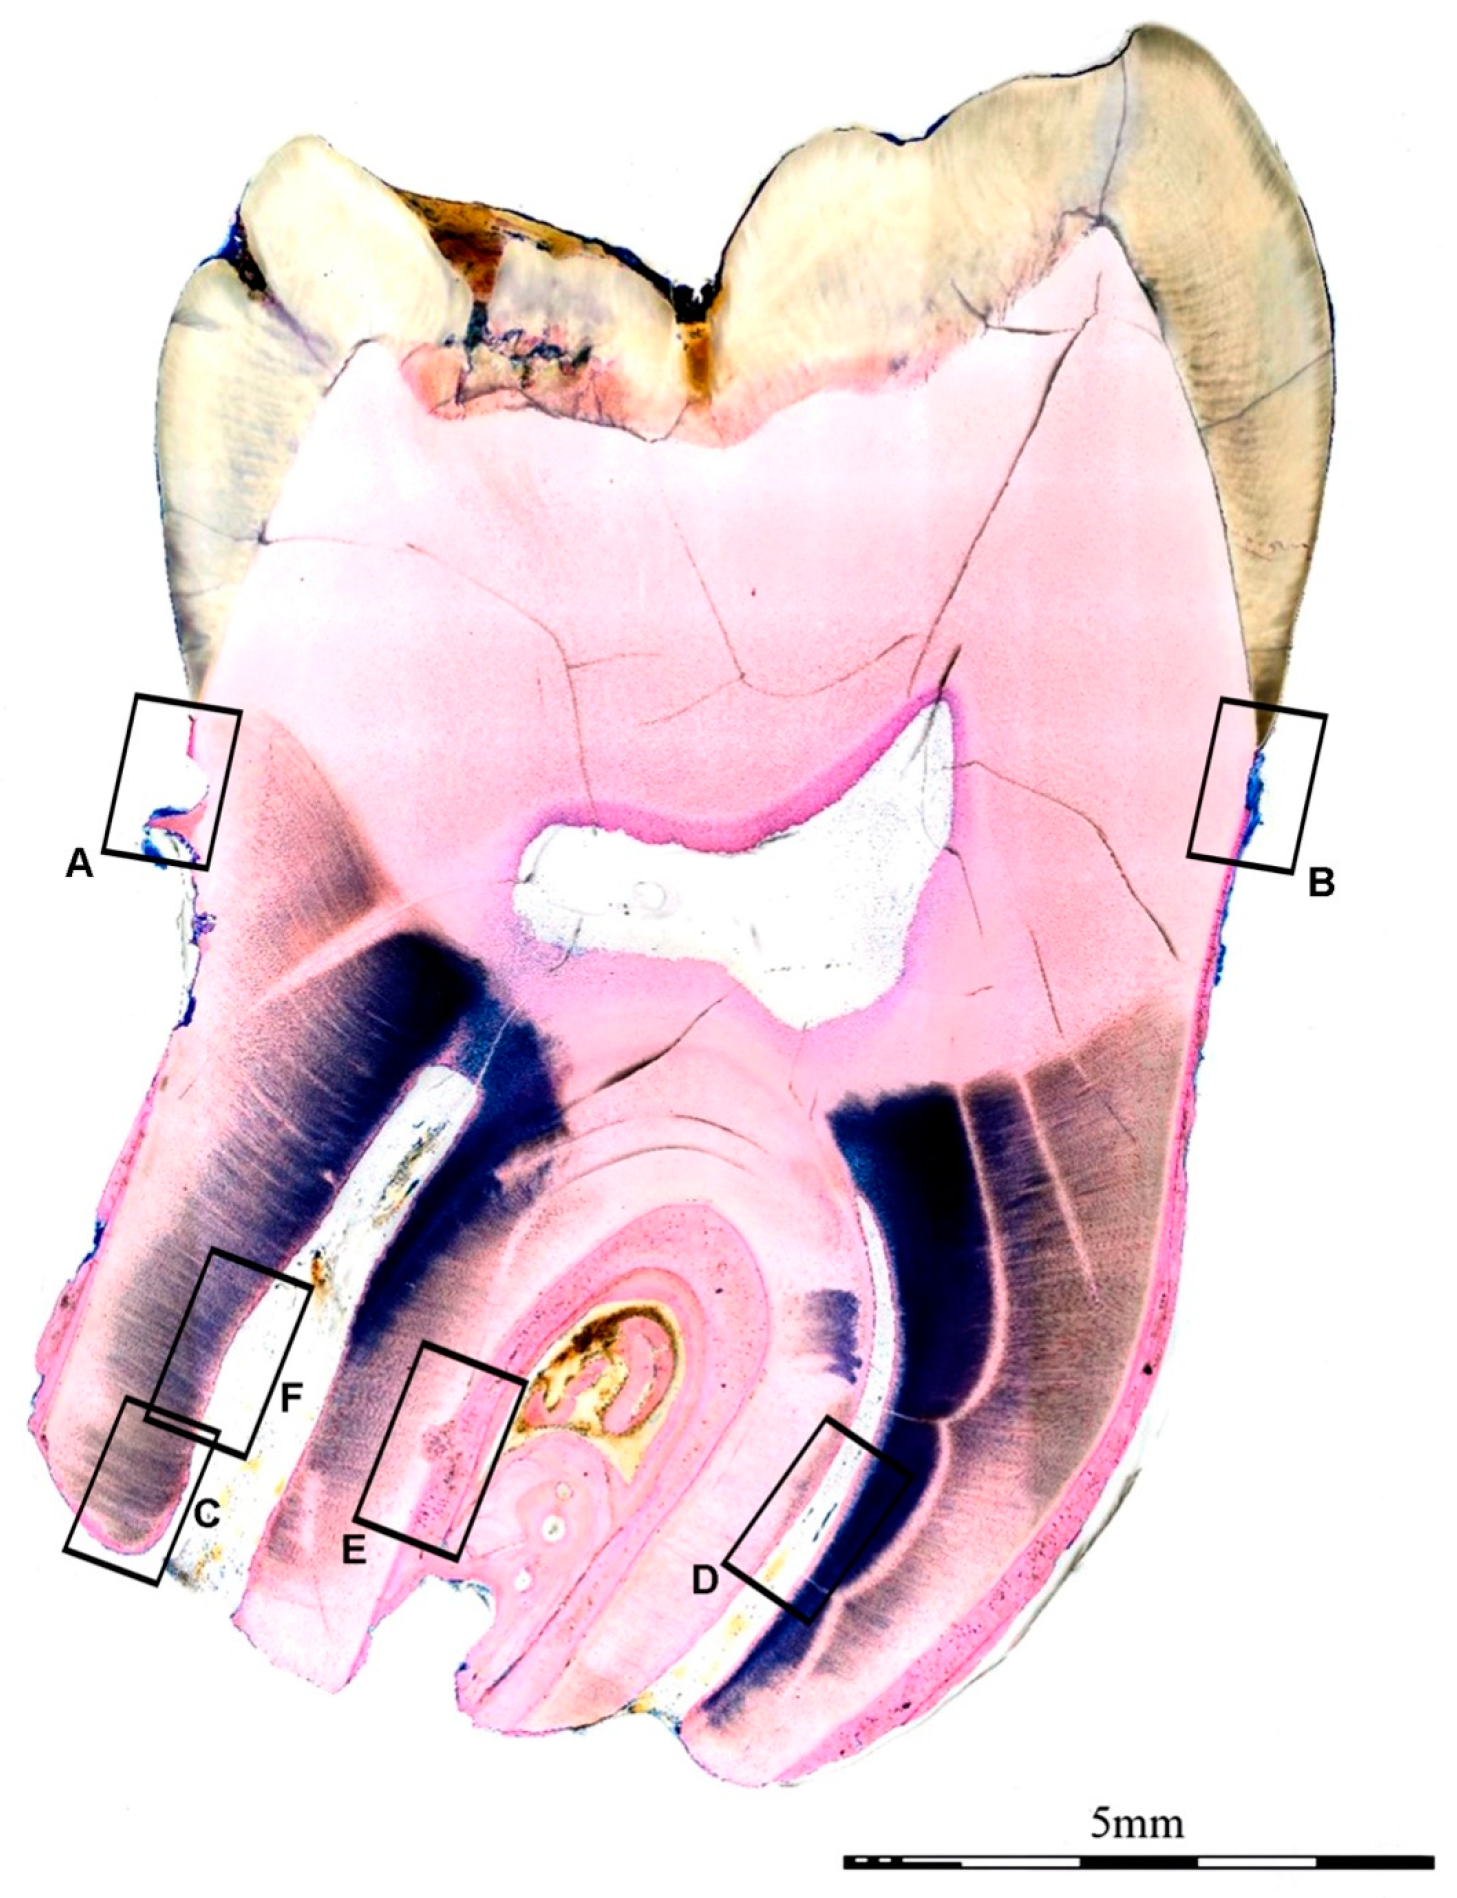

- Donath, K. [The separating thin section technique for the production of histological preparations from tissues and materials that cannot be sectioned: Description of apparatus and methods] German. Die Trenn-Dünnschliff-Technik zur Herstellung histologischer Präparate von nicht schneidbaren Geweben und Materialien. Präparator 1998, 34, 197–206. [Google Scholar]

- Laczko, J.; Levai, G. A simple differential staining method for semi-thin sections of ossyfying cartilage and bone tissue embedded in epoxy resin. Mikroskopie 1975, 31, 1–4. [Google Scholar]